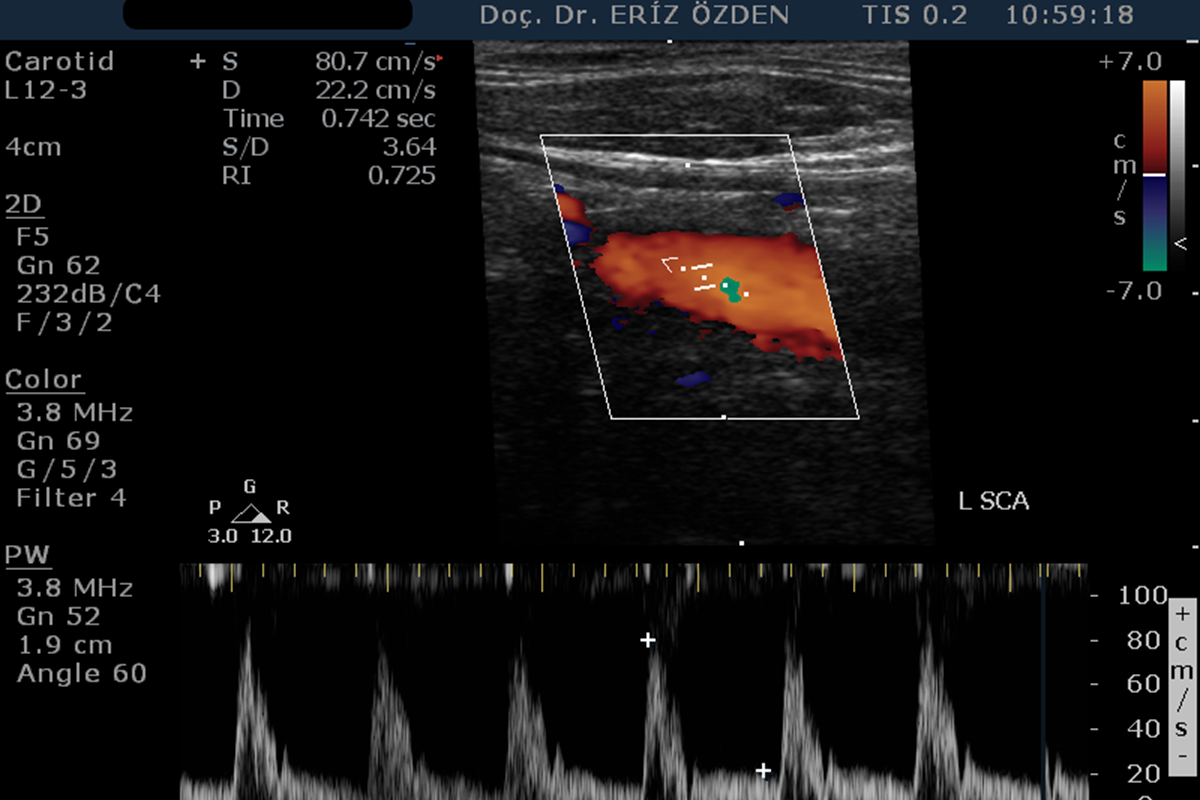

Renkli Doppler Ne Demek, Nasıl Yapılır? Ultrasonografi cihazı Renkli Doppler özelliğine sahipse, damarların içindeki kan akımını renkli olarak görmek mümkündür. Renkli Doppler Ultrason adı verilen bu yöntem sayesinde damarlardaki daralma ve tıkanıklar saptanır. Kan akım hızına yönelik ölçümler yapılır. Kanın damaraı tam olarak doldurup doldurmadığı, kan akımının yönü ve saniyedeki akım miktarı öğrenilir. Özellikle boyun damarlarındaki daralmalarda Karotis Renkli Doppler çok sık kullanılır.

Vertebral Doppler Nedir? Şah damaraı denilen Karotis Arterleri dışında, beyne giden diğer atar damarlara vertebral arter adı verilir. Vertebral arterler beybin arka kısımlarının ve beyinciğin kanlanmasından sorumludur. Bazı hastalarda tukanıklık ya d darlık gelişir ve bu da özellikle baş dönmesi, kulak çınlaması gibi şikayetelre neden olur. Baş dönmesi, dengesizlik şikayetleri olan hastalarda, karotis dopplere ek olarak mutlaka verrebral arter doppler tetkiki de yapılmalıdır.